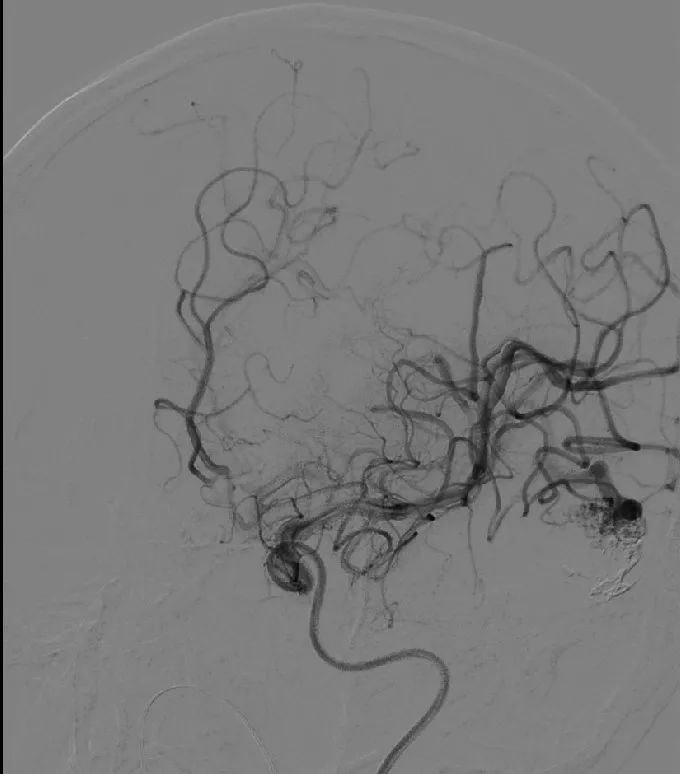

左侧颈动脉造影:左侧颞枕叶可见异常染色,供血动脉为左侧大脑中动脉颞支,引流静脉粗大,向前向下引流至浅静脉。

第一支供血动脉Onyx胶栓塞后造影。

栓塞术后复查造影见畸形团消失,引流静脉通畅,引流静脉较前稍萎缩,引流静脉通畅无滞留。